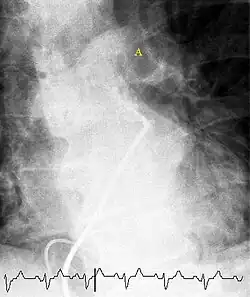

(A) After inhalation of 20 mCi of Xenon-133 gas, scintigraphic images were obtained in the posterior projection, showing uniform ventilation to lungs.

(B) After intravenous injection of 4 mCi of Technetium-99m-labeled albumin, scintigraphic images are shown here in the posterior projection. This and other views showed decreased activity in multiple regions.

A ventilation/perfusion scan (or V/Q scan or lung scintigraphy) shows that some areas of the lung are being ventilated but not perfused with blood (due to obstruction by a clot).[19] This type of examination is as accurate as multislice CT, but is less used, due to the greater availability of CT technology. It is particularly useful in people who have an allergy to iodinated contrast, impaired kidney function, or are pregnant (due to its lower radiation exposure as compared to CT).[66][67][68] The test can be performed with planar two-dimensional imaging, or single-photon emission computed tomography (SPECT) which enables three-dimensional imaging.[59] Hybrid devices combining SPECT and CT (SPECT/CT) further enable anatomic characterization of any abnormality.[69]